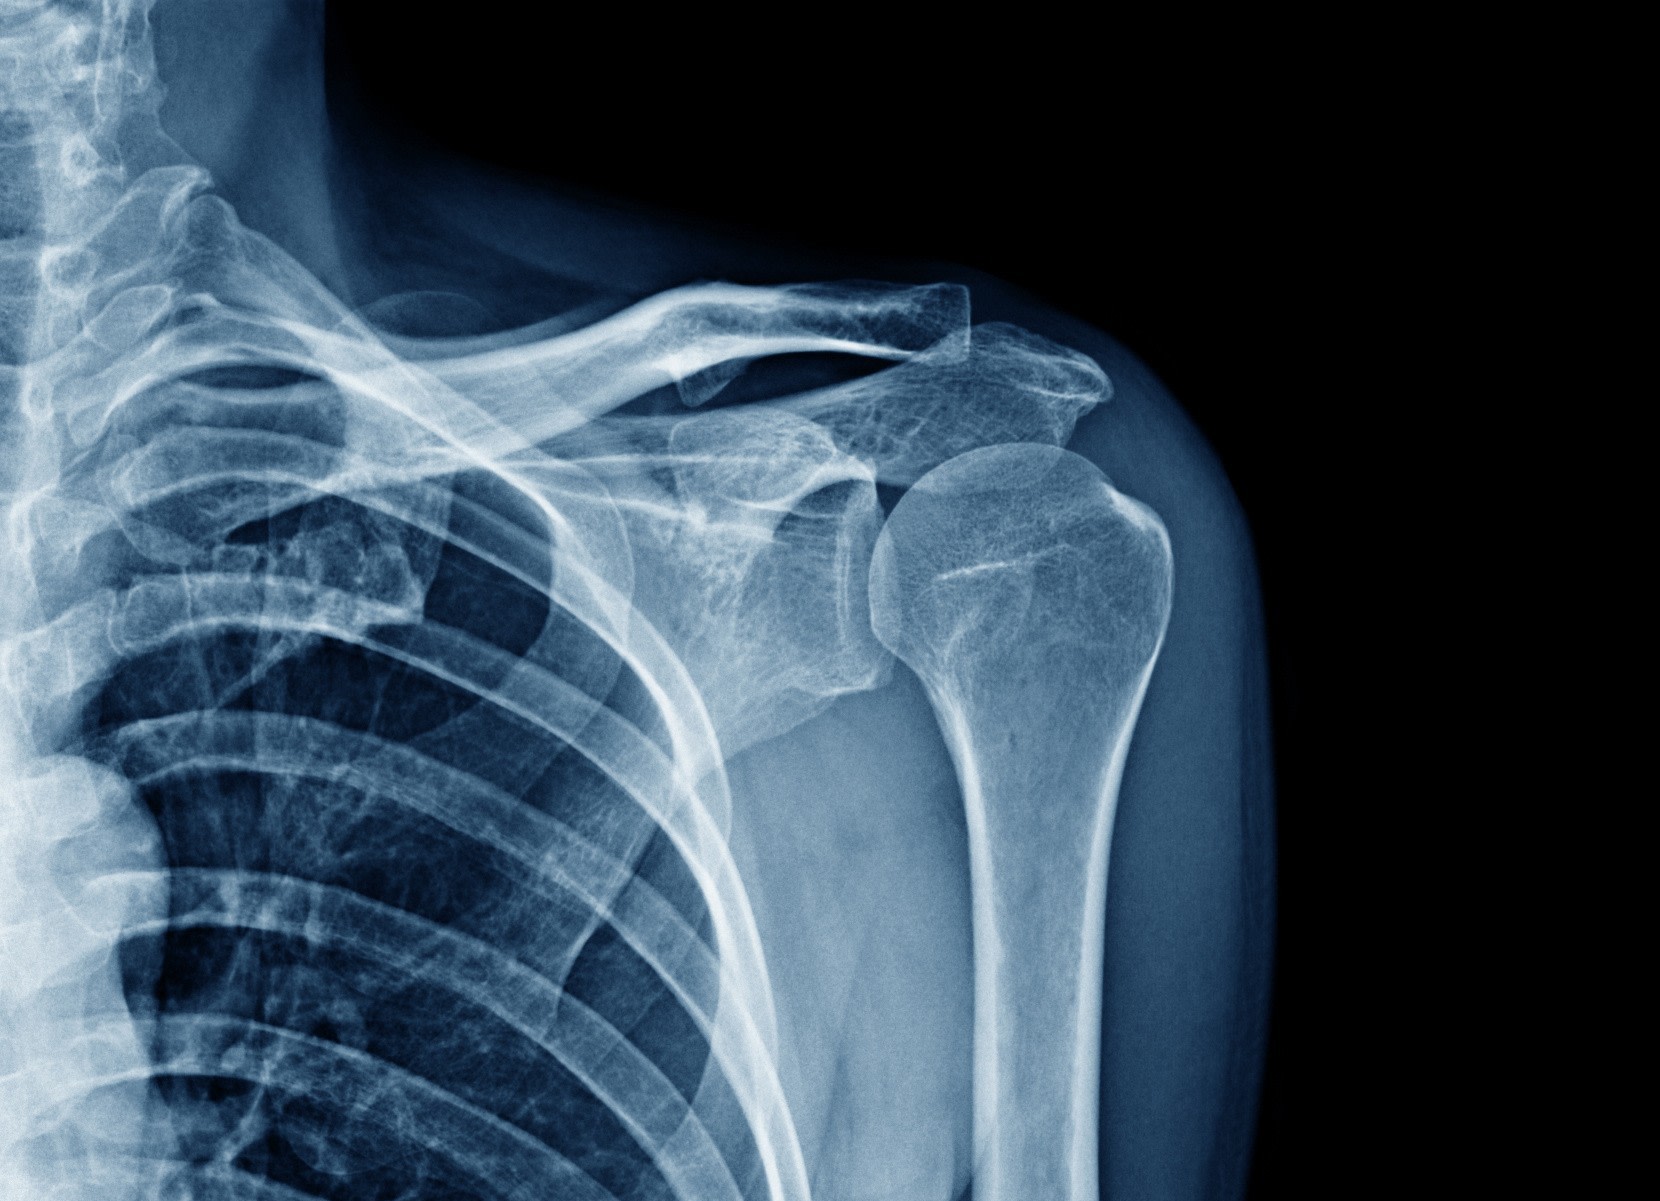

Luxation Gléno-Humérale

- La réduction (urgence) : c'est l'étape où le médecin remet l'articulation en place. Cette manœuvre doit être effectuée par un professionnel de santé, souvent sous antalgiques, après avoir vérifié par radiographie qu’il n’y a pas de fracture.